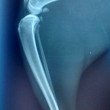

LONDRA – Un gatto è volato giù da un palazzo compiendo un salto di circa 30 metri. Il felino ha riportato una frattura delle gambe posteriori, un polmone collassato e il femore rotto.